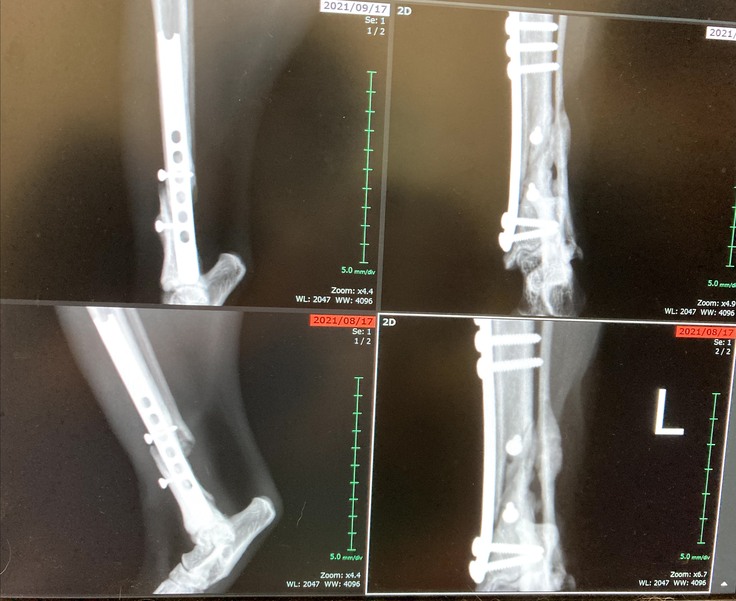

9月17日現在、骨折の方は新しい骨が少しづつ出来てきていました。心配していましたが、良かったです。少しほっとしました。しかし骨形成は遅くまだこれから1か月半位安静必要だそうです。今まで寝てばかりでしたが、最近はお座りも出来るようになってきました。

少しずつ骨もでき元気になって来ています。

9月17日上の写真です。空いていた穴が少しずつ塞がって来ているとの事です。